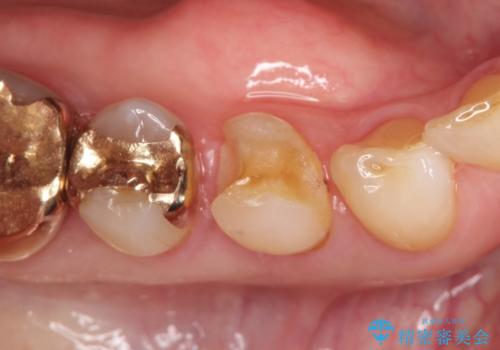

- 他院で治療した金属の詰め物が外れたことを主訴に来院されました。

PGAインレーにて修復治療を行いました。